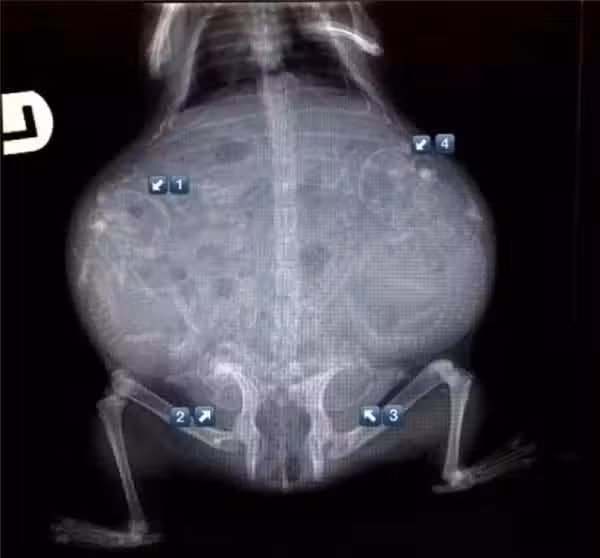

17.雪貂媽媽,雖然不是X光但也一樣驚人